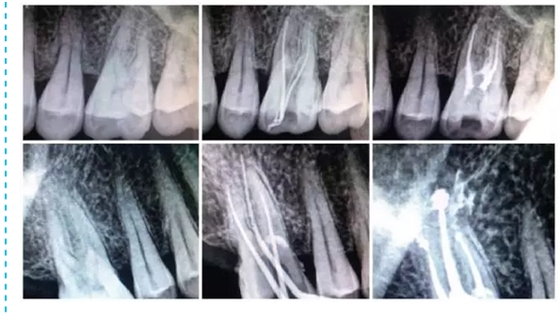

在臨床中選擇使用MM1500音波手機(jī)的基本步驟:選擇病例,急、慢性牙髓炎,根尖周炎,根管無(wú)鈣化,或鈣化根管已疏通,根管無(wú)明顯彎曲者。常規(guī)開(kāi)髓,拔髓。使用手用器械大錐度鎳鈦銼去除根管口牙本質(zhì)領(lǐng),使用10號(hào)或15號(hào)銼針用根管長(zhǎng)度測(cè)量?jī)x測(cè)長(zhǎng),并插入擴(kuò)大針X線根尖片定位。按操作要求,將MM1500音波手機(jī)與牙科綜合治療臺(tái)上渦輪機(jī)工作端相連接,附帶的內(nèi)置式?jīng)_洗裝置使用蒸餾水,氣動(dòng)壓力為30kPa,功率設(shè)置根據(jù)Rispisonic銼針磨損程度,從低檔至中檔選擇,設(shè)置工作長(zhǎng)度,預(yù)彎銼針。以15號(hào)銼針開(kāi)始預(yù)備,始終保持銼針在根管內(nèi)有一定的松動(dòng)空間,與根管壁輕度接觸,并沿根管長(zhǎng)軸提拉,幅度1~2 mm,待銼針可以在根管中較自由進(jìn)出時(shí),以大一號(hào)的手用器械K型銼行標(biāo)準(zhǔn)法修形后換同號(hào)的Rispisonic銼針,同法預(yù)備至所要求的號(hào)數(shù)。每更換一次器械均用新鮮配制2.5 g/L次氯酸鈉溶液沖洗根管,并要求每個(gè)根管至少預(yù)備到比初始號(hào)大兩個(gè)號(hào)以上。預(yù)備過(guò)程中用170g/LEDTA 液和125g/L 次氯酸鈉液交替沖洗根管。預(yù)備后,兩組均用氫氧化鈣糊劑行根管封藥消毒,一周后復(fù)診, 符合根充條件,即行根管充填。試尖合適,采用標(biāo)準(zhǔn)牙膠尖和AH-Plus 根管封閉劑側(cè)向加壓充填法充填根管。根管充填后行常規(guī)X線檢查。改換修復(fù)科進(jìn)行修復(fù)治療。